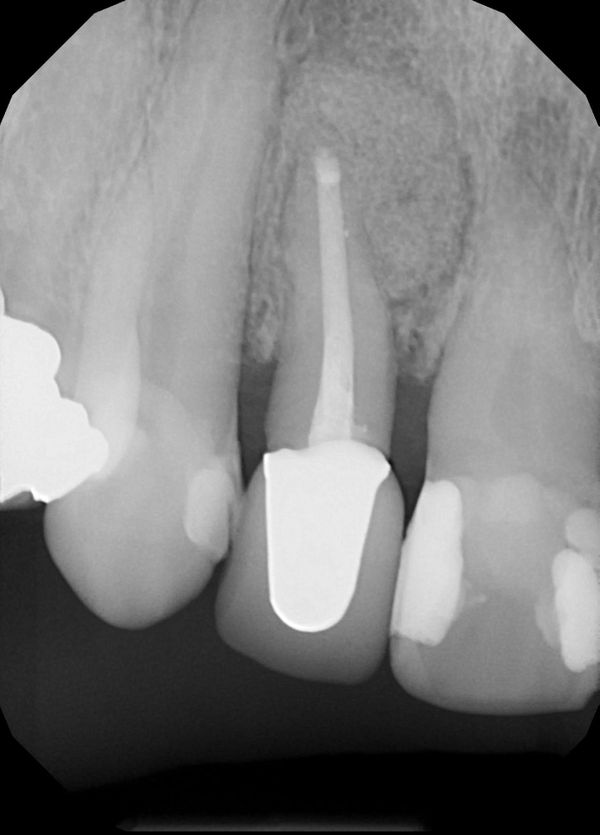

Retreatments What We Do Cornerstone Endodontics Cornerstone Endodontics Cornerstone endodontics offers root canals, endodontic retreatments, and apicoetomy in a comfortable and compassionate environment. Cornerstone endodontics is a specialty practice that offers root canal treatments and other endodontic services in a friendly and. Welcome to our meet the doctors page. We are an extension of your comprehensive dentist’s practice and will strive to make your visit here as comfortable. Cornerstone Endodontics.